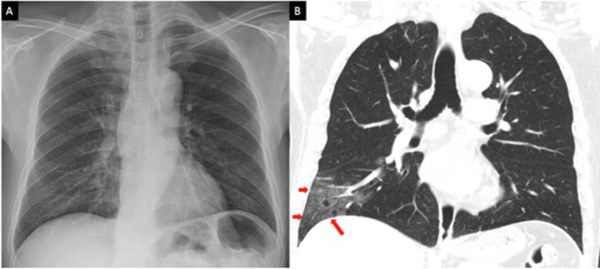

Hình ảnh phổi tổn thương của bệnh nhân nhiễm Covid-19

Không phải bất cứ ai nhiễm virus cũng đều có triệu chứng và tổn thương phổi. Tuy nhiên, nghiên cứu có khoảng 25% bệnh nhân khi nhiễm virus, đầu tiên là virus Sars-CoV-2 xâm nhập tế bào, hình thành nên ổ virus; tiếp theo là gây rối loạn hệ miễn dịch (ví dụ hội chứng bão cytokine); và cuối cùng là gây tổn thương phổi trong đó có đông đặc phổi hay còn gọi là gan hóa phổi.

Đối với đại dịch Covid-19 qua các báo cáo, nghiên cứu, khám nghiệm tử thi của bệnh nhân Covid-19 đều thấy bệnh nhân có biểu hiện của đông đặc phổi cấp và tử vong vì suy hô hấp cấp. Đây được xem là "sát thủ" của bệnh nhân Covid-19.

Bác sĩ Nam cho biết bình thường nhu mô phổi xốp nhưng khi nhu mô phổi bị viêm, các phế nang xung huyết chứa đầy dịch tiết, tỷ trọng nhu mô phổi tăng được biểu hiện lâm sàng bằng hội chứng đông đặc.